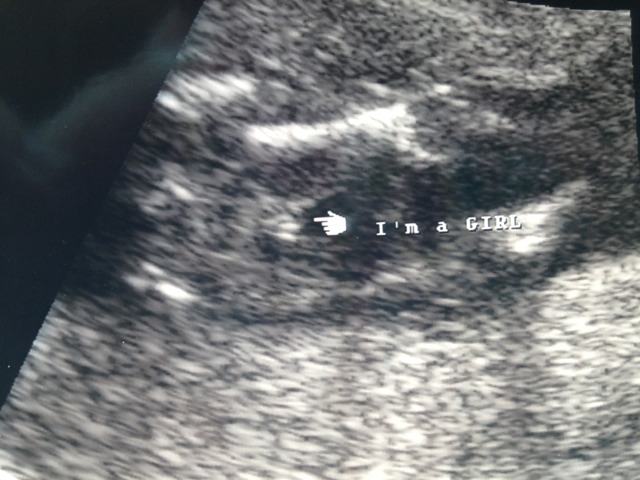

Tech was very confident. Looks girly to me but would love other opinions?? Here are two different views.